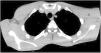

Chest x-ray showed a large left lung pneumothorax; a chest tube was successfully placed with clinical improvement and total lung expansion. Thoracic computer tomography (Figures 1 and 2) revealed hypoplasia of the major pectoralis muscle confirming the diagnosis of Poland Syndrome and ruled out other abnormalities. There was full resolution of the pneumothorax and the chest tube was removed after four days.